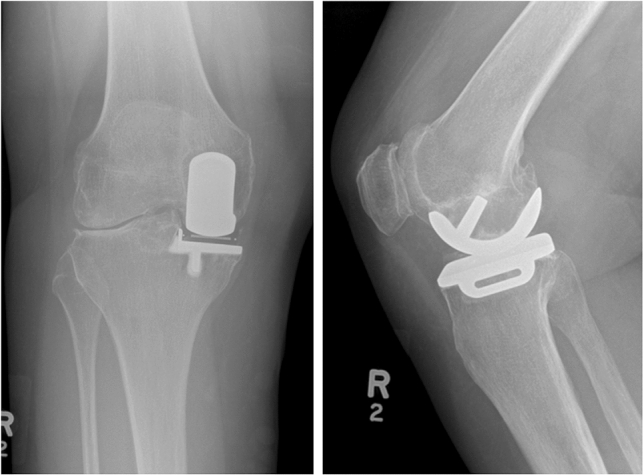

UKA mediale vs UKA laterale: differenze pratiche

UKA mediale (AMOA come scenario tipico)

Pattern classico: usura antero-mediale, compartimento laterale preservato, ACL funzionale, deformità in varo correggibile.

UKA laterale

Meno frequente e più “selettiva” per anatomia/biomeccanica, ma con indicazioni ben descritte:

OA laterale moderata-severa con compartimento mediale a cartilagine a tutto spessore, legamenti integri, deformità in valgo correggibile e contrattura limitata (spesso <10–15°). Controindicazioni ricorrenti: artrite infiammatoria e coinvolgimento patello-femorale severo.